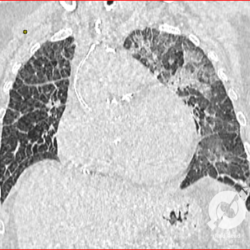

Lesões intersticiais reticulares difusas, cardiomegalia, derrame pleural á direita (Rx)/Opacidades em vidro fosco, cardiomegalia e aumento do calibre das estruturas venosas.